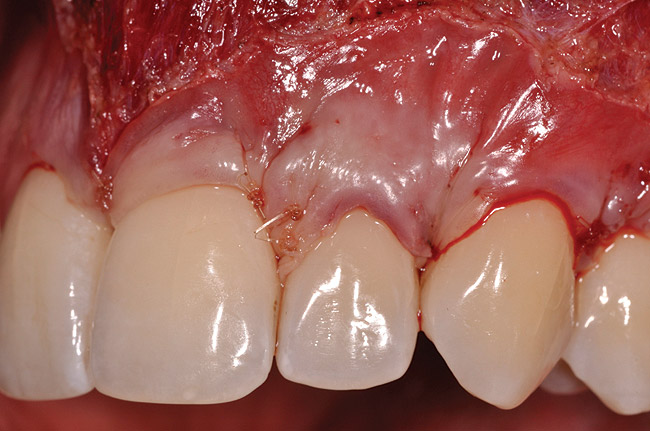

The flap approach follows an incision design where the crest of the papilla is preserved and a V-type incision is made in the papillary tissues (Figure 4). This allows the preexisting papillary tissues in the area just inferior to the contact point of the natural teeth affected to be used as a tissue bed to provide vascularization to the flap/dermis complex. Prior to securing the dermal matrix tissue, the papillary tissues that remain after the incision technique outlined must be de-keratinized by using a #4 round diamond bur. This allows for the introduction of initial blood flow and vascularization of the dermal matrix tissues and nourishment of the coronally repositioned flap in the critical area of the interproximal papillary tissues. After securing the dermal matrix tissue from the palatal/lingual aspect of the teeth being treated and coronally repositioning the buccal flap, closure is achieved using an interrupted sling suturing technique.

After initial incision techniques were done, a papillary-sparing incision was performed, leaving the crest of the papilla intact (Figure 10), thus allowing flap closure to be accomplished with a bed of autogenous tissue to support revascularization of the dermis/buccal flap complex. A full-thickness flap was then elevated to the mucogingival junction, after which a split-thickness dissection with a blunt elevator superior to the mucogingival junction area was performed to allow for release of tension and to let the buccal flap be mobilized coronally at closure (Figure 10). Care must be taken to avoid perforating the tissue in the region of the vestibuloplasty incision. After tension-free release of the flap, root planing of the exposed root surfaces was accomplished, followed by removal of the smear layer of cementum and chemical detoxification with a citric acid solution pH1 applied over the previously root-planed surfaces. After root preparation, the keratinized papillary tissues that remained following initial incisions were de-keratinized by using a #4 round diamond on a high-speed handpiece. De-keratinization provided a wound bed that enabled the dermal matrix graft to be secured and supported revascularization of the coronally repositioned buccal flap at closure.

Fig 4. V-type incision to preserve the crestal portion of the papilla.

Figure 4